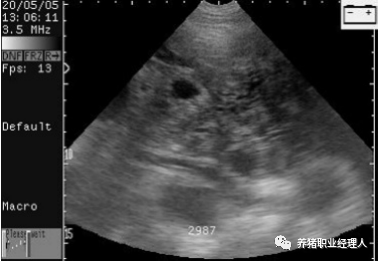

至少要发现3个不同的胚囊,才可判断为妊娠。

由于时间匆忙而将暗的斑点看成是胚胎。

将卵巢上的囊肿与胚胎混淆。

有囊肿的空怀母猪。这头母猪永远不会怀孕。

有一个副卵巢囊肿的母猪。这头母猪能够怀孕。

扫描配种第24天的母猪,大的胚胎囊可以很容易的看到。